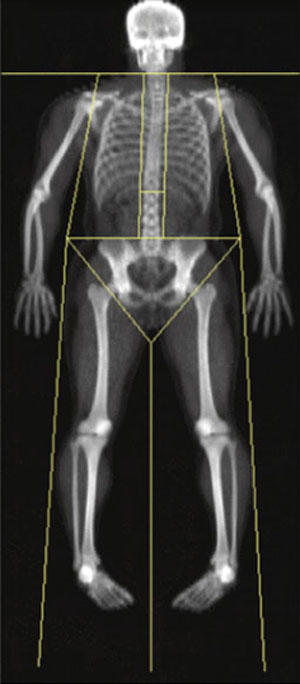

Researchers at the Wellcome Trust Sanger Institute led an international consortium of investigators from Canada, Israel, the Netherlands and UK to study approximately 20,000 individuals, searching for regions in the genome that were associated with differences in height. By looking through 300,000 known SNPs – single letter changes in genetic code – the team found 17 regions that contributed to human height. To understand better how variation at these regions contributed to height, the team took skeletal measurements of the spine, leg and hip-axis, to determine the specific effects of these genetic markers on the length of skeletal size measurements.

The team wanted to elucidate how the 17 variants strongly associated with adult height impacted on the length of individual skeletal components. To measure the length of the skeletal components the team used data from high-resolution densitometric scans of human bones. Nine of the variants were associated with increased trunk length; approximately 5 per cent of the variance in femur length was explained by a combination of all of the variants. Seven of the variants influenced hip-axis length, which is a known predictor for osteoporosis in humans.